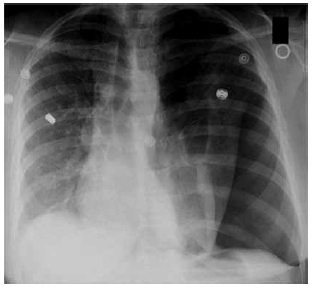

Homem, 55 anos, encontra-se internado para tratamento da covid-19. No décimo sexto dia da doença, tendo sido extubado há 48 horas, recebeu alta para a enfermaria, onde permaneceu em uso de cateter nasal de O2 2 L/min. Encontra-se em uso de enoxaparina 40 mg, metilprednisolona 40 mg/dia e esomeprazol. Antecedentes pessoais: tabagista, com carga tabágica de 60 maços-ano, e obeso. Durante a noite, apresentou episódio de dispneia súbita, associada à dor torácica à esquerda, sendo necessária máscara de Venturi 50% para manter SpO2 em torno de 91%. Neste momento, o exame clínico do paciente apresentava os seguintes achados relevantes: PA = 110 x 70 mmHg, FC = 110 bpm, SpO2 = 92%, FR = 26 ipm; ausculta pulmonar abolida em hemitórax esquerdo, com estertores difusos em hemitórax direito.

A radiografia de tórax encontra-se a seguir.